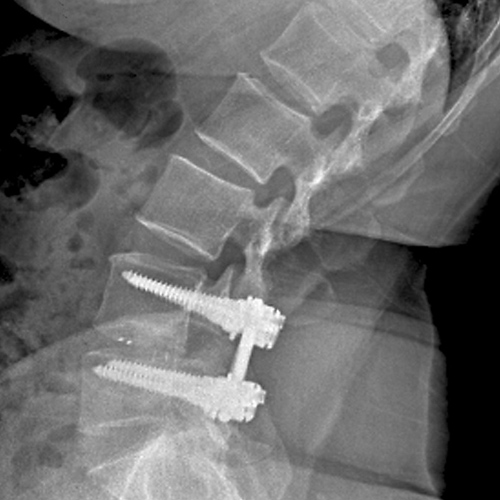

척추고정술

척추관 협착이나 기타 변형으로 인해 불안정한 척추를 스크류로 안정화시켜 수술 후 조기 보행과 유합율을 높여 줍니다.

협착증이 있는 부분에 요추 후궁절제술로 척수신경을 충분히 풀어 준 다음에 척추의 불안정증을 교정하기 위하여 기구(스크류)를 이용하여 척추를 고정하는 수술입니다.